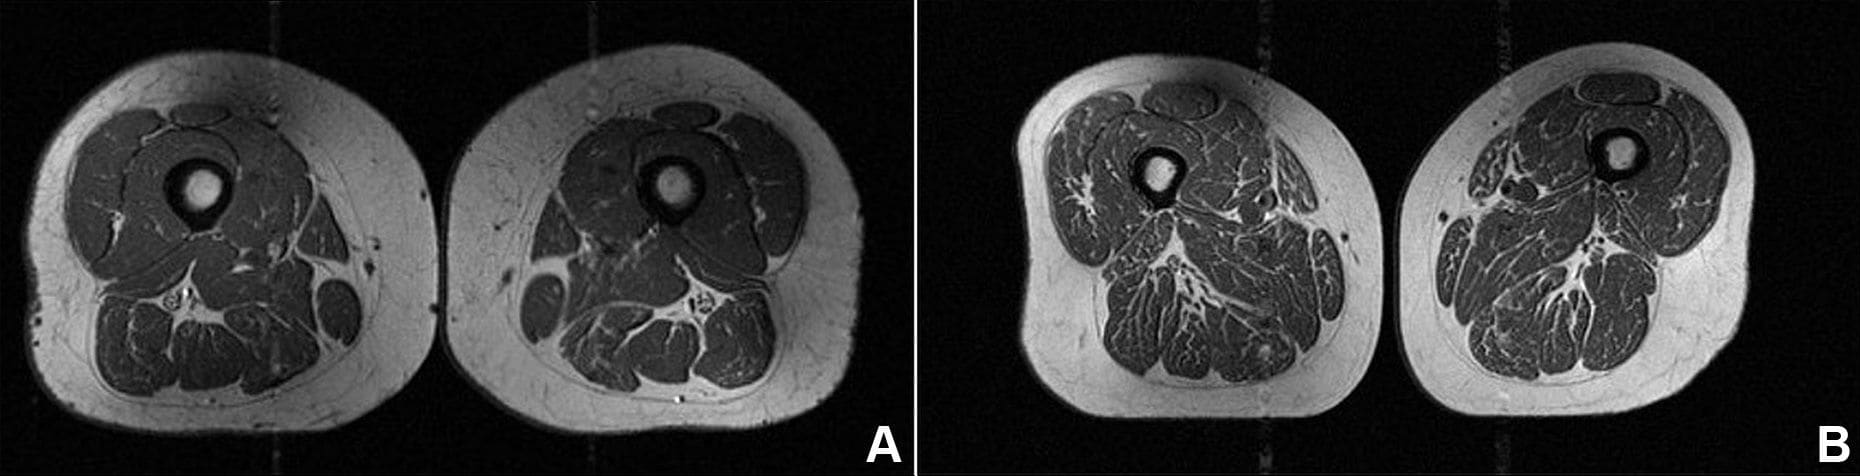

هذه ليس شريحة لحم بل فخذ امرأة.. هكذا تدمر الأطعمة فائقة المعالجة جودة عضلاتك شاهد مقاطع فيديو ذات صلة دبي، الإمارات العربية المتحدة (CNN)-- تبدو هذه الصورة أشبه بشريحة لحم تتمتّع بدرجة عالية من الترخيم (توزيع الدهون)، على نحو قد يذكّرك بقطع اللحم الفاخرة في المطاعم، الغنية بخيوط دقيقة من الدهون المتداخلة.

لكن تُظهر هذه الصورة تصويرًا بالرنين المغناطيسي (MRI) لفخذ امرأة تبلغ من العمر 62 عامًا، كانت تحصل على 87% من سعراتها الحرارية السنوية من الأطعمة فائقة المعالجة.

كما أظهرت امرأة أخرى في الدراسة، تبلغ من العمر 61 عامًا، وجود ترخيم دهني في عضلات فخذها، لكنه كان أقل حدة، إذ شكّلت الأطعمة فائقة المعالجة نحو 29% من نظامها الغذائي السنوي.

وقالت أكّايا: "كان ذلك مقلقًا لأنّ هؤلاء الأفراد الذين خضعوا للتصوير في وقت لم تظهر لديهم فيه أي علامات على التهاب الركبة، كانوا بالفعل يُظهرون تدهورًا في جودة العضلات".